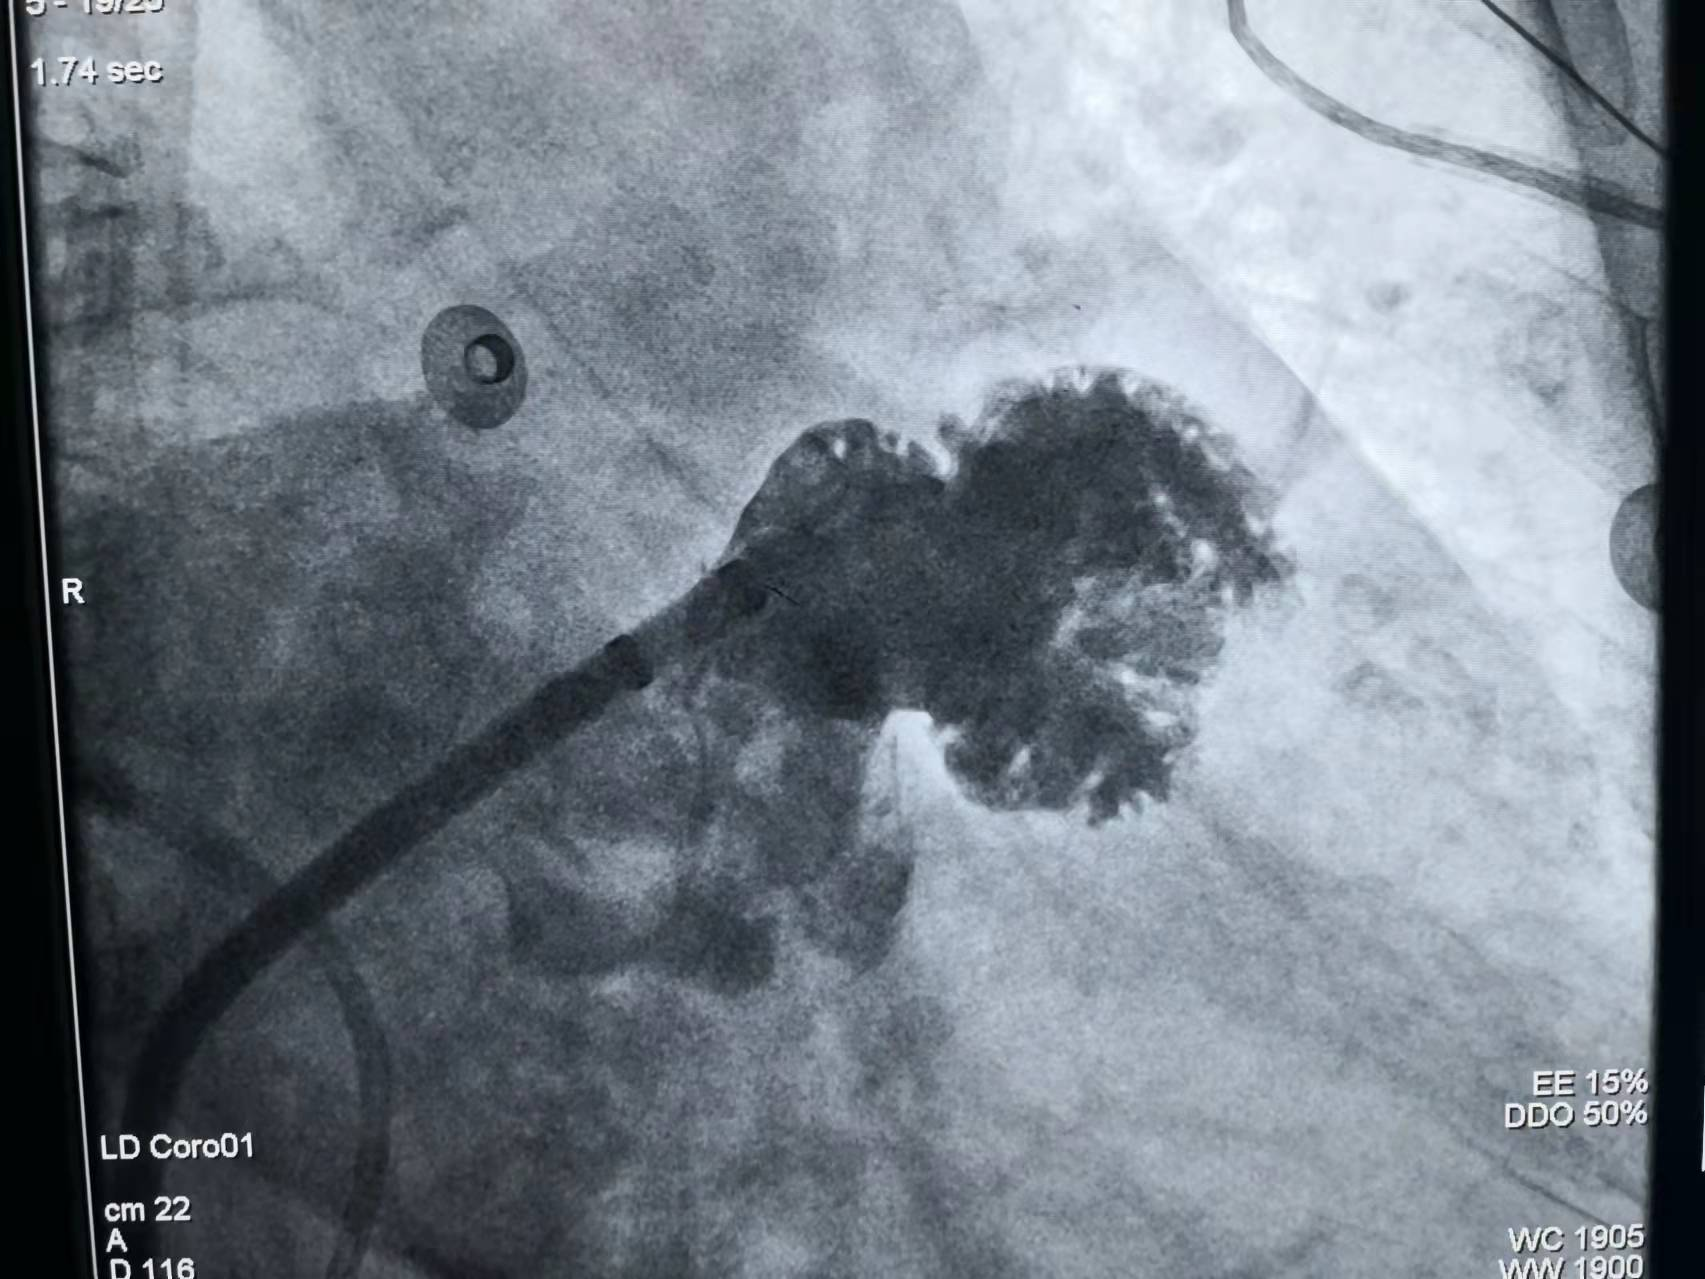

入院后,市九院心脏中心心血管内科一病区袁清茹主任、胡号兵副主任医师详细询问病史了解病情,钱阿姨为阵发性房颤病史长,已导致心功能不全,给患者日常生活带来严重的困扰,心理负担重,焦虑,失眠,患者因患有甲状腺功能减退,不适宜应用治疗房颤常用的胺碘酮,为预防血栓既往服用抗凝药物后出现皮肤瘀斑,牙龈出血,泌尿道出血等。心脏中心主任、心血管介入中心主任赵明中博士查看患者后指出:该患者长期受房颤严重困扰,心脏较前轻度增大,出现了心功能不全症状,且房颤发作自觉症状明显并造成严重心理负担,且老年患者,合并多种疾病,治疗需个体化。心脏彩超提示心房轻度增大,适宜射频消融术恢复正常的窦性节律、控制快速房颤发作症状;根据CHA2DS2-VASc评分6分,血栓栓塞风险高,HAS-BLED评分4分,抗凝出血风险高,须防治血栓栓塞,且患者不能耐受抗凝治疗,有明确左心耳封堵术适应证,建议射频消融术加左心耳封堵术一站式手术,患者本次住院的主要目的也是希望在郑州市九院心脏中心能用先进的心血管介入技术来帮助自己解除多年的疾病困扰。

市九院心脏中心赵明中主任,心血管内科一病区袁清茹主任带领一病区团队致力于老年房颤的规范化管理,为每一位房颤患者制定合适的个体化方案,使多位房颤患者显著获益。钱阿姨享受到了一站式的医疗技术服务,她对医护人员说到:“心脏不像以往那样乱跳了,血栓栓塞风险大大降低了,也不用长期口服抗凝药物了”。